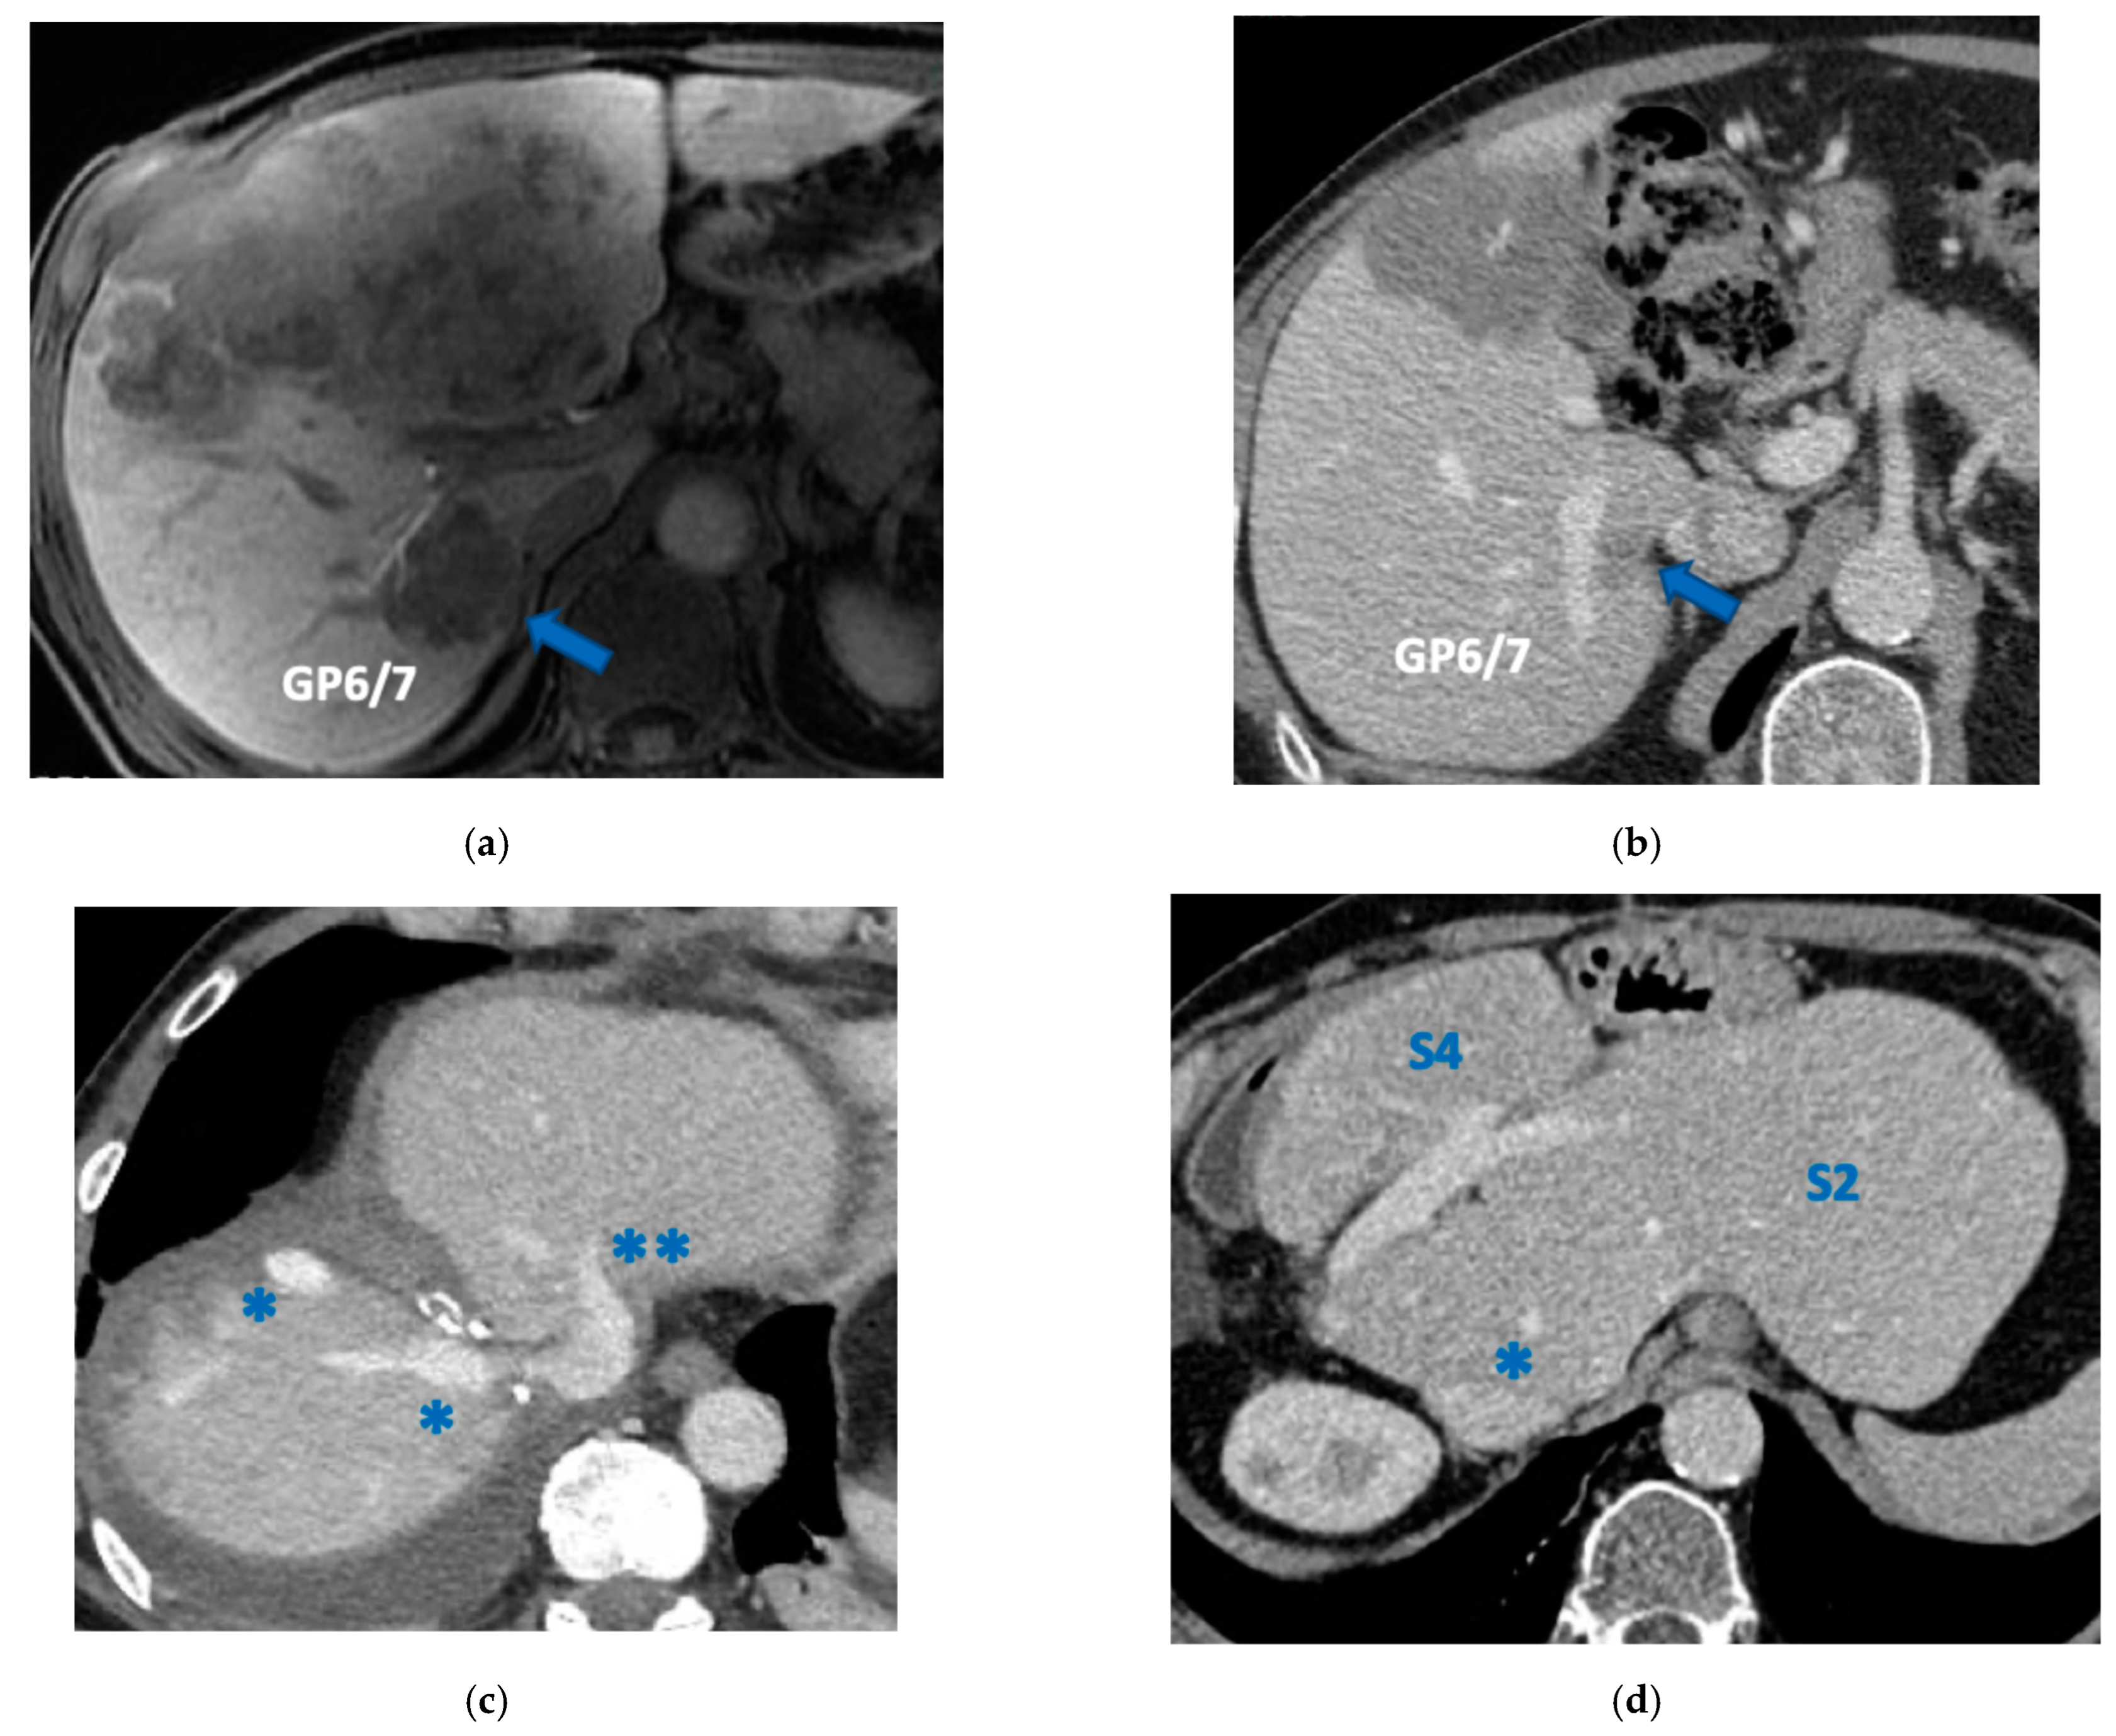

In six patients the resection of first-order GP was planned and e-ALPPS was performed. Four e-ALPPS were parenchyma sparing since a part of S4 was preserved (in deportalized liver in one case of FLR = part of S6/S7, see Figure 9).

In four cases the Spiegel lobe was preserved. At the first stage (MLP) MHV was resected in four cases, preserved in deportalized liver in the case of FLR = part of S6/S7 and reconstructed with an end-to-lateral anastomosis with LHV (FLR = S4b/S2/Spiegel lobe) in one case. In two patients (FLR 15% = part of S4/S2 and Spiegel lobe; FLR 7% = part of S2/S3) FLR volume was deemed inadequate after the first step of e-ALPPS (FLR 29% and 28%, 15 and 17 days after the first stage), daily liver growth after the first stage was 21 mL/day in the first 8 days and 8 mL/day in the subsequent 7 days in one case and 19 mL/day in the first 17 days in the other (in the latter, growth kinetic cannot be evaluated during the first week since CT was not performed). Intermediate stage of partial resection of the deportalized liver was performed (in both cases resection of S5-S8, in one case en-bloc with RHV which was reconstructed with an end-to-end anastomosis). Seven days after the intermediate stage FLR volume increased up to 39% and 41% with a daily growth of 18 mL/day and 25 mL/day. The third stage to complete the ALPPS procedure was performed (23 and 27 days after the first stage) resecting the last part of deportalized liver (S6/S7). In both cases the left hemicolectomy was associated to third step of staged e-ALPPS (see Figure 10, Figure 11, Figure 12 and Figure 13).

Taking into account that the liver can be considered a paired organ, we introduced the concept of e-ALPPS when first-order GP resection is planned and FLR volume is deemed insufficient. ALPPS is defined as enhanced because liver partition is obtained with two full thickness transection lines (MLP) instead of the single line as described in the classical ALPPS [6] with the advantage of leaving a well-vascularized liver parenchyma with no possibility for parenchymal debris. We have added to ALPPS the parenchyma-sparing concept, expanding the novelty introduced by Botea et al. [20] of preserving S4 whenever possible including the deportalized liver (Figure 9).